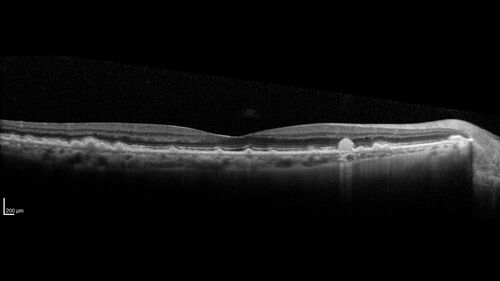

Intermediate Dry Age-Related Macular Degeneration - Soft Drusen

70-year-old Left eye worse than the right.  Both eyes see distortion in the amsler grid for a few months

HTN, High Lipids, Osteoporosis

Meds: Lutein once daily, Calcium, Fish oil, Red Yeast Rice, CoQ10, Magnesium, MVI, Xanax

VA 20/16 OU

2+NS cataract